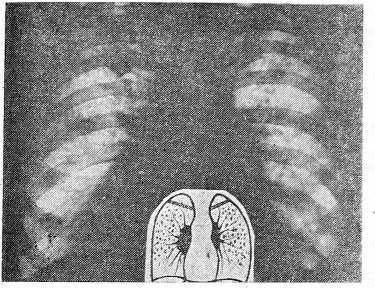

При дифференциальной диагностике крупноочагового карциноматоза с туберкулезом следует учитывать и то обстоятельство, что для свежего диссеминированного туберкулеза нехарактерны очаги крупных размеров, а если они и выявляются, то, как правило, в верхне-задних отделах за счет слияния более мелких. Крупноочаговые тени в средних и нижних отделах при гематогенном туберкулезе обычно свидетельствуют о наличии распада с бронхогенным обсеменением и, в дополнении с данными о бацилловыделении, не представляют серьезных диагностических трудностей. Известно, что чем мельче очаги при гематогенном туберкулезе легких, тем меньше вероятность их слияния и распада и тем менее типична локализация. Поэтому наибольшие затруднения встречаются при дифференциальной диагностике милиарных и мелкоочаговых диссеминаций. В этих случаях может иметь значение увеличение густоты очаговых теней в передне-заднем направлении, что отмечается у большинства больных диссеминированным туберкулезом и нехарактерно для неспецифических дис- семинаций. Этот признак хорошо выявляется при сравнительной оценке серии фронтальных томограмм.

- У второй группы больных наблюдались множественные метастазы, среди которых по размеру можно выделить 2 варианта: мелкие (до 1 см в диаметре) и крупные. По существу, они являются этапами развития одного процесса, и если при диссеминированном карциноматозе значительный рост очагов констатируется не всегда из-за быстрой гибели больных, то при множественных метастазах его можно видеть постоянно. Выделение этой группы целесообразно потому, что общей, объединяющей чертой является сравнительно небольшое количество очаговых теней — от 2—3 до нескольких десятков. Поэтому спутать их с диссеминированным туберкулезом практически невозможно. При подобном рентгенологическом синдроме кроме рака можно скорее предположить множественные метастазы альвеококка, цистицеркоз, пневмонию и множественные туберкулемы (рис. 5, 6).

Крупные множественные метастазы, создающие картину, известную как симптом «разменной монеты», выявляются на более поздних этапах развития. Величина их, в отличие от мелких метастазов, часто бывает различной, что может зависеть от неравномерности роста метастазов, связанной, вероятно, с неодинаковыми условиями местной трофики, а также от нескольких волн метастазирования. Крупные множе-, ственные метастазы имели, как правило, ту же характеристику контуров, что и мелкие, были гомогенными и не имели связи с корнем. Распад множественных метастазов мы наблюдали лишь у 2 больных.

Симптом «разменной монеты» не типичен для туберкулеза. Множественные туберкулемы встречаются нередко, однако, в отличие от множественных метастазов, число их обычно не превышает 2—3; располагаются они чаще в апикодорсальной зоне группами, в пределах одного сегмента или доли, нередко имеют включения извести и очаги в окружающей легочной ткани, а более крупные из них часто распадаются.